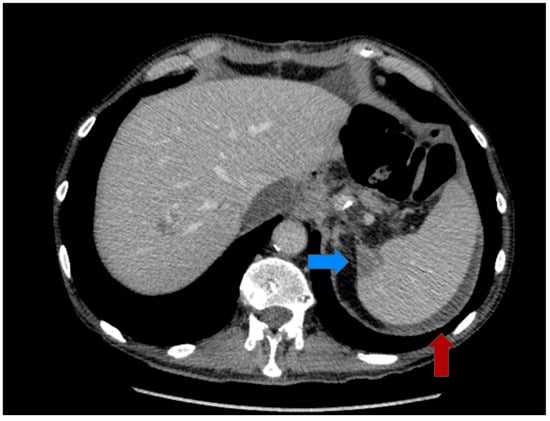

2.2. Multimodal Approach and Treatment

2.3. Postoperative Course